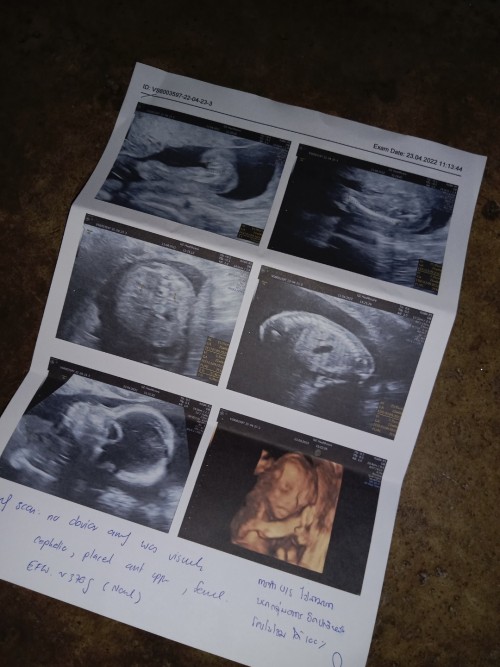

3 มิติค่ะแม่